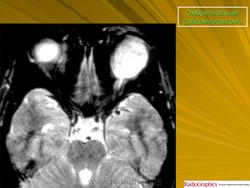

Рабдомиосаркома — чрезвычайно агрессивная опухоль орбиты, является наиболее частой причиной злокачественного роста в орбите у детей. Мальчики болеют почти в 2 раза чаще. Источником роста рабдомиосаркомы являются клетки скелетных мышц. Выделены три типа опухоли: эмбриональный, альвеолярный и плеоморфный, или дифференцированный. Последний тип встречается редко. У детей до 5 лет чаще развивается эмбриональный тип опухоли, после 5 лет — альвеолярный. Как правило, рабдомиосаркома состоит из элементов нескольких типов (смешанный вариант). Точный диагноз можно установить только на основании результатов электронной микроскопии.

Излюбленная локализация опухоли — верхневнутренний квадрант орбиты, поэтому в процесс рано вовлекаются мышца, поднимающая верхнее веко, и верхняя прямая мышца. Птоз, ограничение движений глаза, смещение его книзу и книзу кнутри — это первые признаки, на которые обращают внимание как сами больные, так и окружающие лица. У детей экзофтальм или смещение глаза при локализации опухоли в переднем отделе орбиты развивается в течение нескольких недель (рис. 20.23, а). У взрослых опухоль растет медленнее, в течение нескольких месяцев. Быстрое увеличение экзофтальма сопровождается появлением застойных изменений в эписклеральных венах, глазная щель полностью не смыкается, отмечаются инфильтраты на роговице и ее изъязвление. На глазном дне — застойный диск зрительного нерва. Первично развиваясь вблизи верхневнутренней стенки орбиты, опухоль быстро разрушает прилежащую тонкую костную стенку, прорастает в полость носа, вызывая носовые кровотечения. Ультразвуковое сканирование, компьютерная томография, термография и тонкоигольная аспирационная биопсия — это оптимальный диагностический комплекс инструментальных методов исследования при рабдомиосаркоме (рис. 20.23, б). Лечение комбинированное. Протокол лечения предусматривает предварительное проведение полихимиотерапии в течение 2 нед, после чего проводят наружное облучение орбиты. После комбинированного лечения более 3 лет живут 71 % больных.